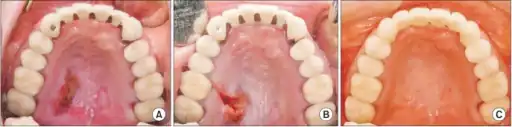

Necrotizing sialometaplasia (NS) is a benign, ulcerative lesion, usually located towards the back of the hard palate. It is thought to be caused by ischemic necrosis (death of tissue due to lack of blood supply) of minor salivary glands in response to trauma. Often painless, the condition is self-limiting and should heal in 6–10 weeks.

Although entirely benign and requiring no treatment, due to its similar appearance to oral cancer, it is sometimes misdiagnosed as malignant. Therefore, it is considered an important condition, despite its rarity.

Initially, the lesion is a tender, erythematous (red) swelling. Later, in the ulcerated stage, the overlying mucosa breaks down to leave a deep, well-circumscribed ulcer which is yellow-gray in color and has a lobular base.[1]